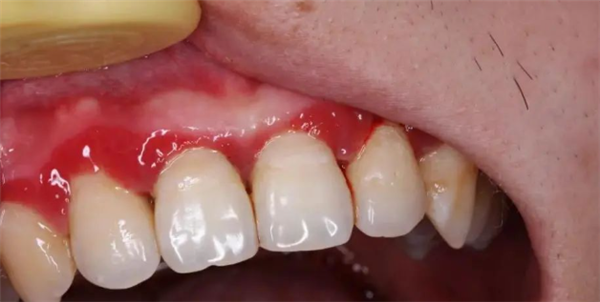

一开始出现的症状大概率是:牙龈有点发红、刷牙的时候有点出血,或者啃一口苹果后发现留下了一圈血印子。

刚开始,仅仅是出现牙龈红肿及出血,并不一定导致疼痛,图源:作者提供 刚开始,仅仅是出现牙龈红肿及出血,并不一定导致疼痛,图源:作者提供 慢慢地,你不在意,牙龈只是有点退缩,然后牙齿缝慢慢显露出来,露出难看的黑三角。